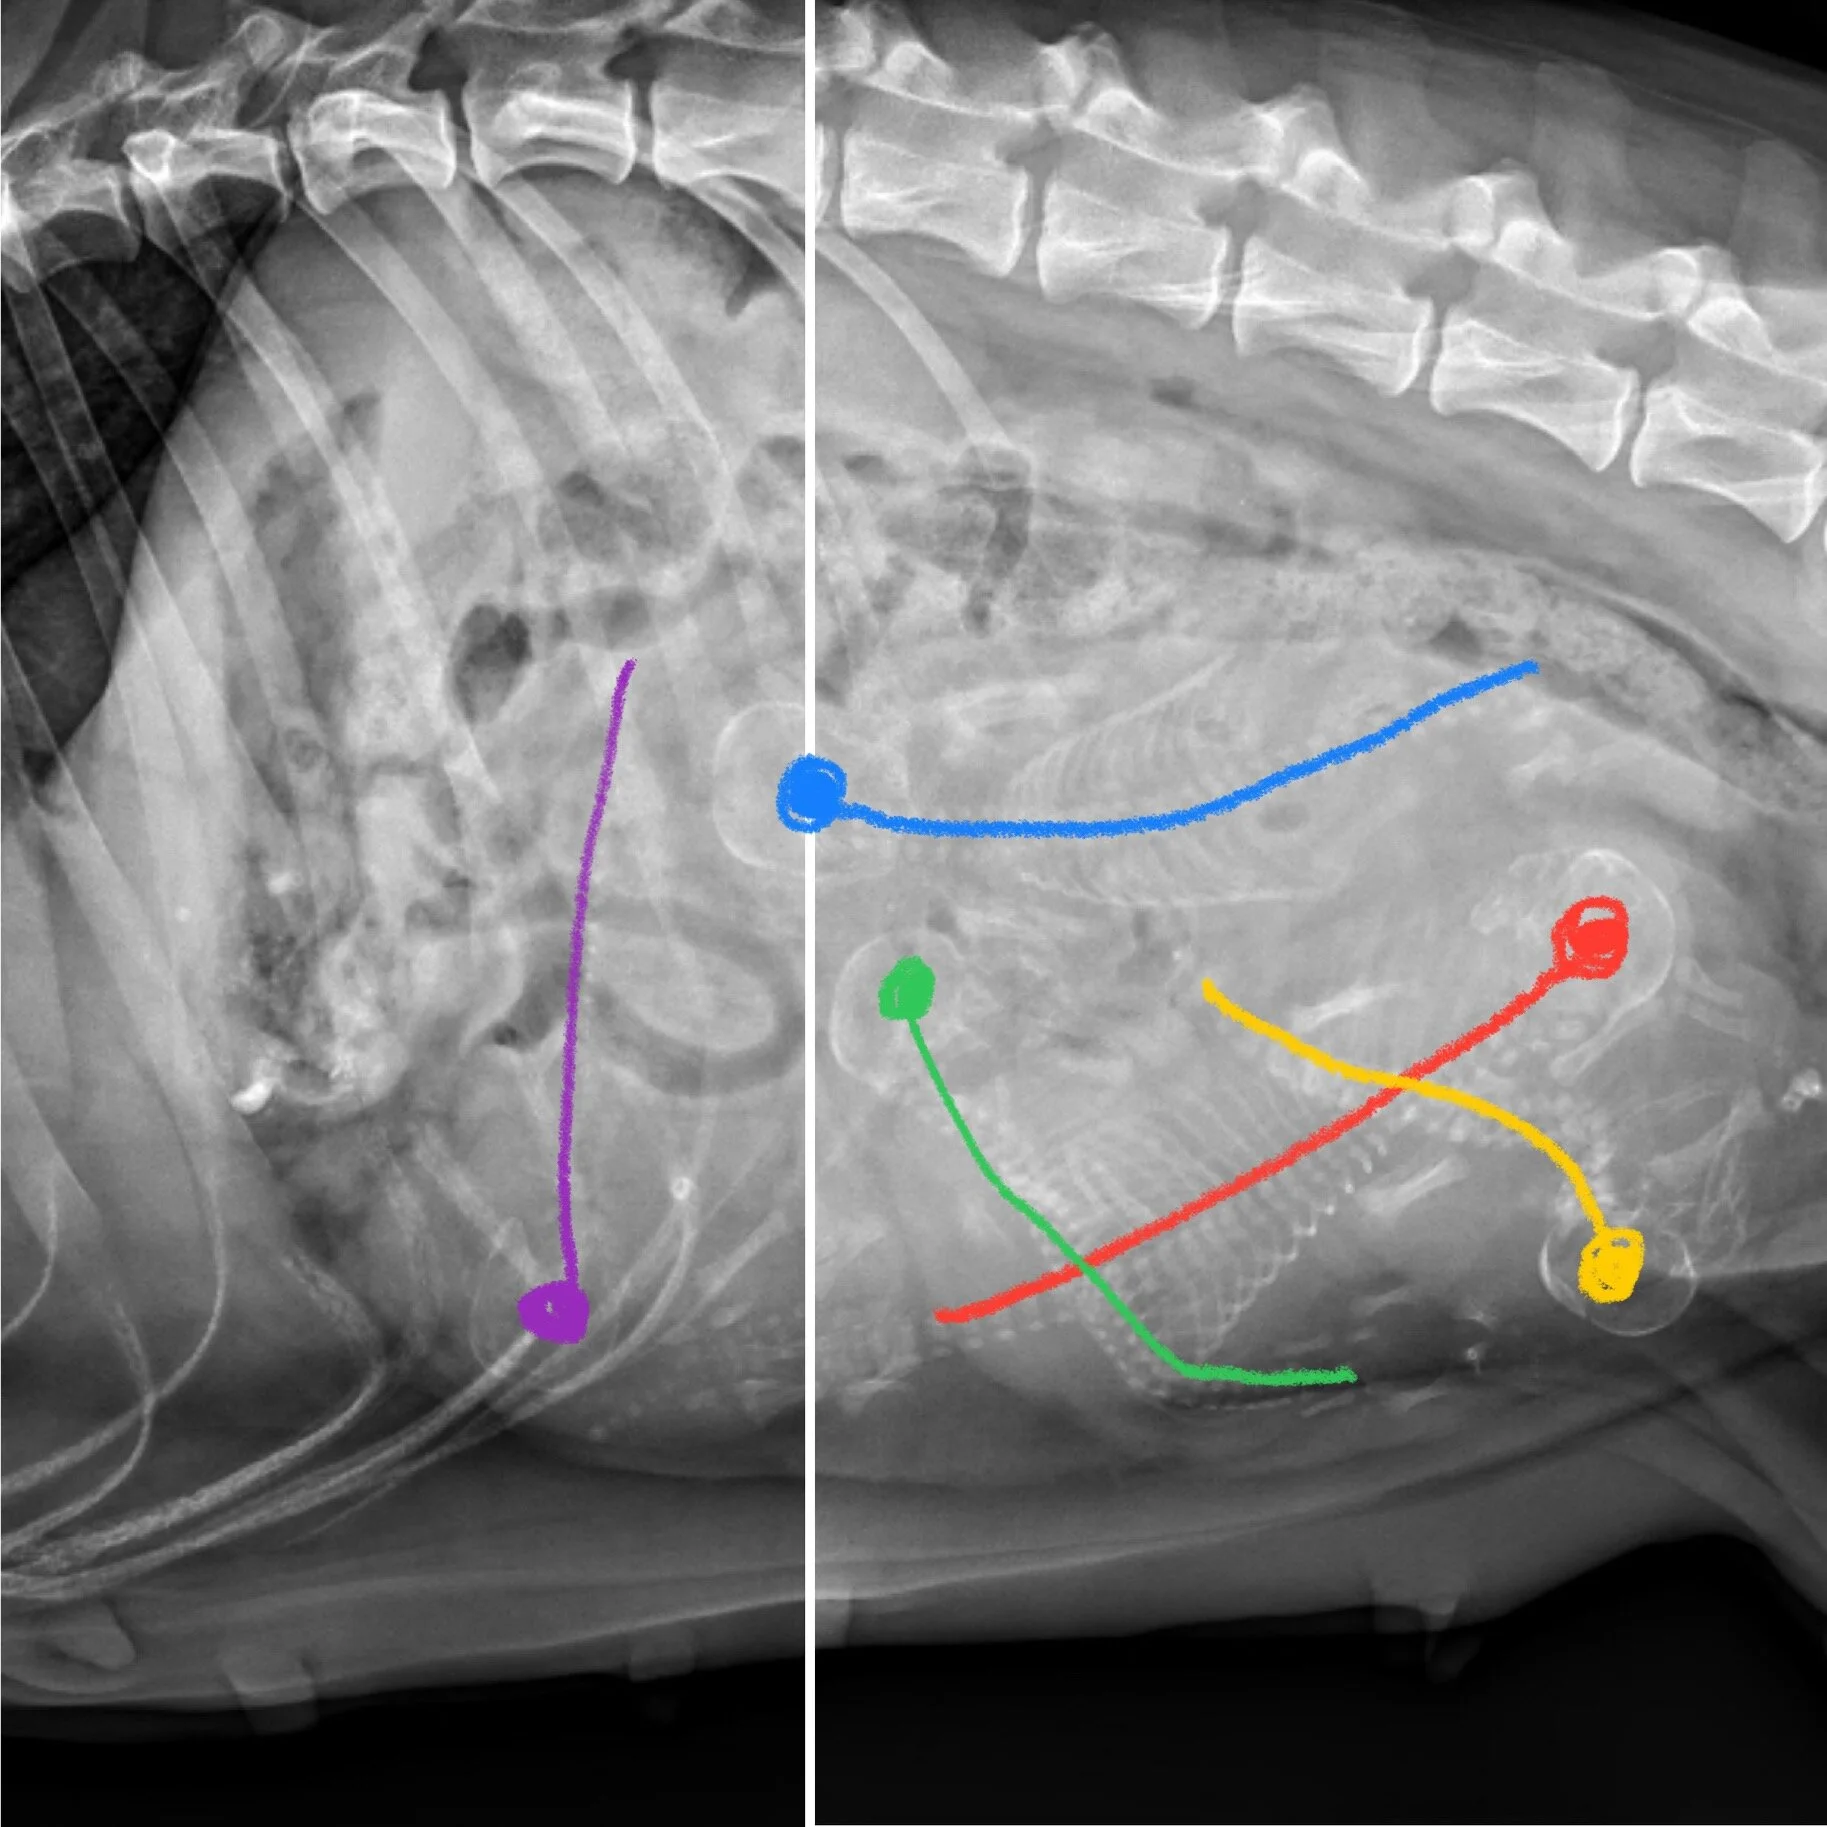

Dogs are pregnant for approximately 9 weeks, or 63 days. During this time, our job is to keep the mother well fed, well exercised, and relatively stress-free. The mother will visit our veterinarian at least three times—once for a prenatal health check, once for an ultrasound, and once for an x-ray. The first ultrasound is to simply confirm her pregnancy so we can begin accepting deposits and preparing to whelp. The X-Ray is for later in the pregnancy to get a more accurate count on how many puppies we are expecting. The mother is fed with proper nutrition as recommended by our veterinarian as well as prenatal and postnatal supplements.